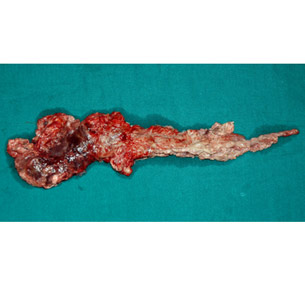

Resected specimen after Whipple's procedure

Resected specimen showing ampullary cancer